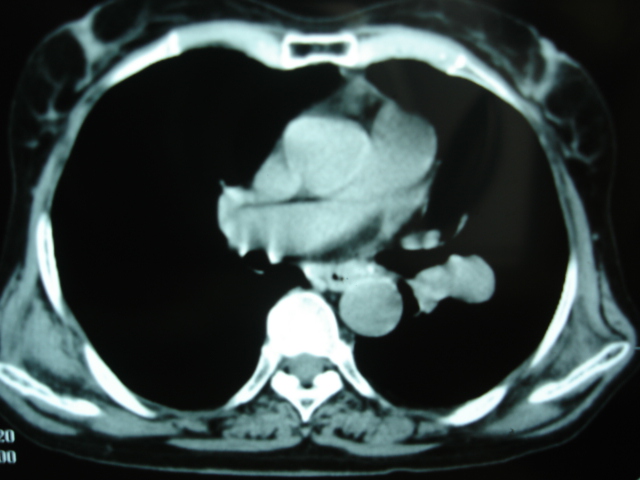

以下是引用卜一在2009-9-7 19:51:00的发言:[br][br] 1 左侧胸内甲状腺占位-多考虑甲状腺腺瘤! 2、左肺门占位-建议增强扫描以便明确性质。 3 慢支并感染! [br]

以下是引用shibing在2009-9-7 20:40:00的发言:[br]左侧胸内甲状腺占位-多考虑甲状腺腺瘤! 2、左肺门占位-建议增强扫描以便明确性质。 3 慢支并感染! [br]